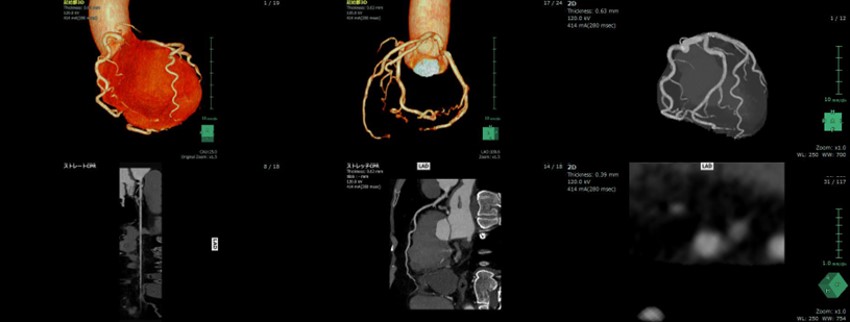

Fig6. VR画像およびMPR画像

③ 最適心位相検索の自動化による検査ワークフロー向上

当院では、アブレーション治療の手術支援画像として肺静脈造影CTを行っている。

その際に、しばしば冠動脈も同時に撮影を依頼されることがある。この場合、必然的に不整脈患者が対象となるため、安定した心拍で撮影することができず、画像再構成のための心位相検索が技師の大きな負担となる。今回導入したRevolution CTにはSmartPhaseという自動的に最適な心位相を自動的に検索を行う機能が搭載されている 。SmartPhaseは、指定した心位相範囲を2%間隔で画像再構成し、各冠動脈の動きを分析する。その中でモーションアーチファクトが小さい心位相を自動的に選択し、画像を作成する。この機能により、従来技師が行っていた心位相検索が、自動かつ高精度で行われることで、技師の負担と冠動脈CT検査のハードルが大幅に低くなった。

さらに、前述したSSF2.0と組み合わせて使用することができるため、技師の負担軽減と良好な画像の作成の両立が可能となった(Fig7)。

RevolutionCT_koyamakinen07.jpg

Fig7. 不整脈患者に用いたSmart Phaseの再構成画像